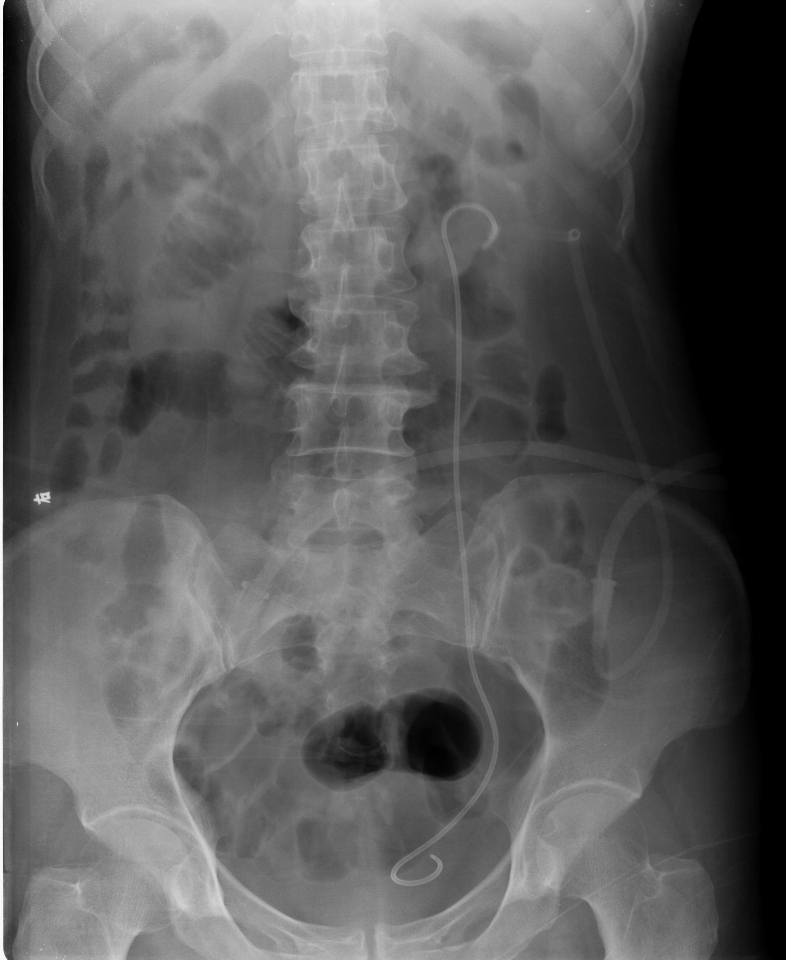

碎石前典型病例1                  碎石后典型病例1

碎石前典型病例2                  碎石后典型病例2